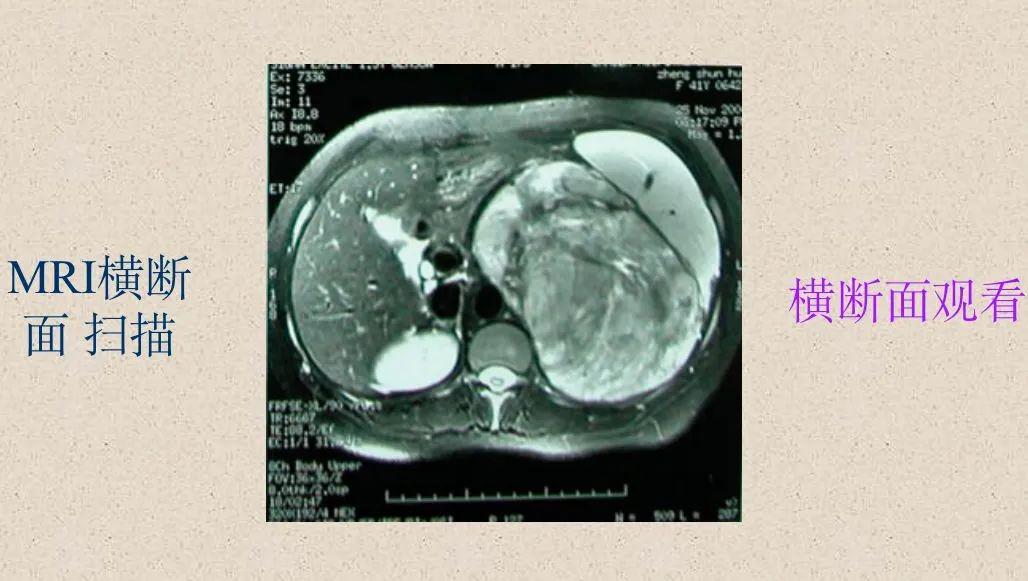

横断面(水平面或轴面)– 将身体分成上下两部分

椎管形态:在横断面上椎管各段的形状及大小存在差异